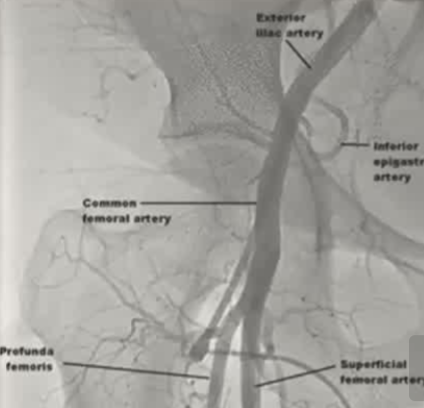

| 学习目标 1. 学习替代性动脉通路的适用情况及操作方法 2. 根据特定标准筛选出适合采用替代性动脉通路的患者 3. 为了明确不同动脉通路的优缺点 需要考虑的股动脉接入参数 股动脉对侧入路法:不从病变同侧的股动脉穿刺,而是从健康的股动脉穿刺,翻过腹主动脉分叉,去治疗对侧的血管病变

可酌情处理髂动脉和股总动脉病变。

对侧入路特别适合处理髂总动脉、髂外动脉起始部以及股总动脉的病变。因为这些位置如果从同侧顺血流方向做,穿刺点正好在病变附近甚至需要穿过病变,压迫止血困难或支架定位空间不够;而从对侧翻过来,刚好可以避开穿刺点,从容定位

1. 直达病变,路径直接Ipsilateral approach: Straightforward approach to the lesion |